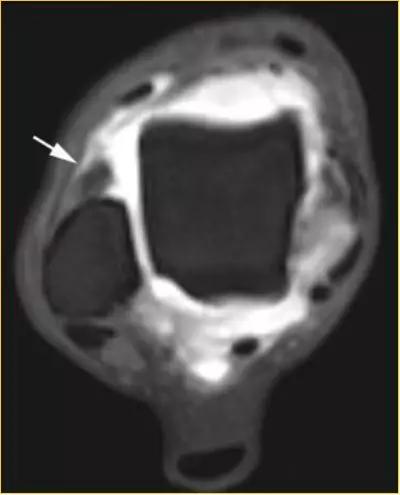

- 影像学表现为外侧沟内异常软组织或(和)前胫腓韧带(AITFL)异常肥厚。

①踝关节外侧沟内异常软组织

②前胫腓韧带(AITFL)异常肥厚

T1WI FS C+

异常增厚的前胫腓韧带